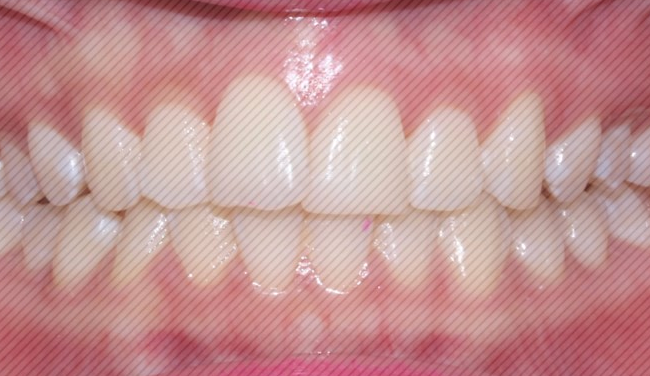

2D교정 교정기간 : 4개월

상악 오른쪽 앞니의 부분 돌출도

이상없이 고르게 교정이

완료 되었습니다.

하악 크라우딩

(자리가 없어 덧난 경우) 도

예쁘게 제자리를 찾아 갔습니다.

4개월만에 개선된 모습을 보니

환자분도 굉장히 만족해하셨는데요.

대신 그만큼 유지장치도

잘 착용해주시고

관리도 잘 해주셔야 한다는 점!

잊지 마세요 :)